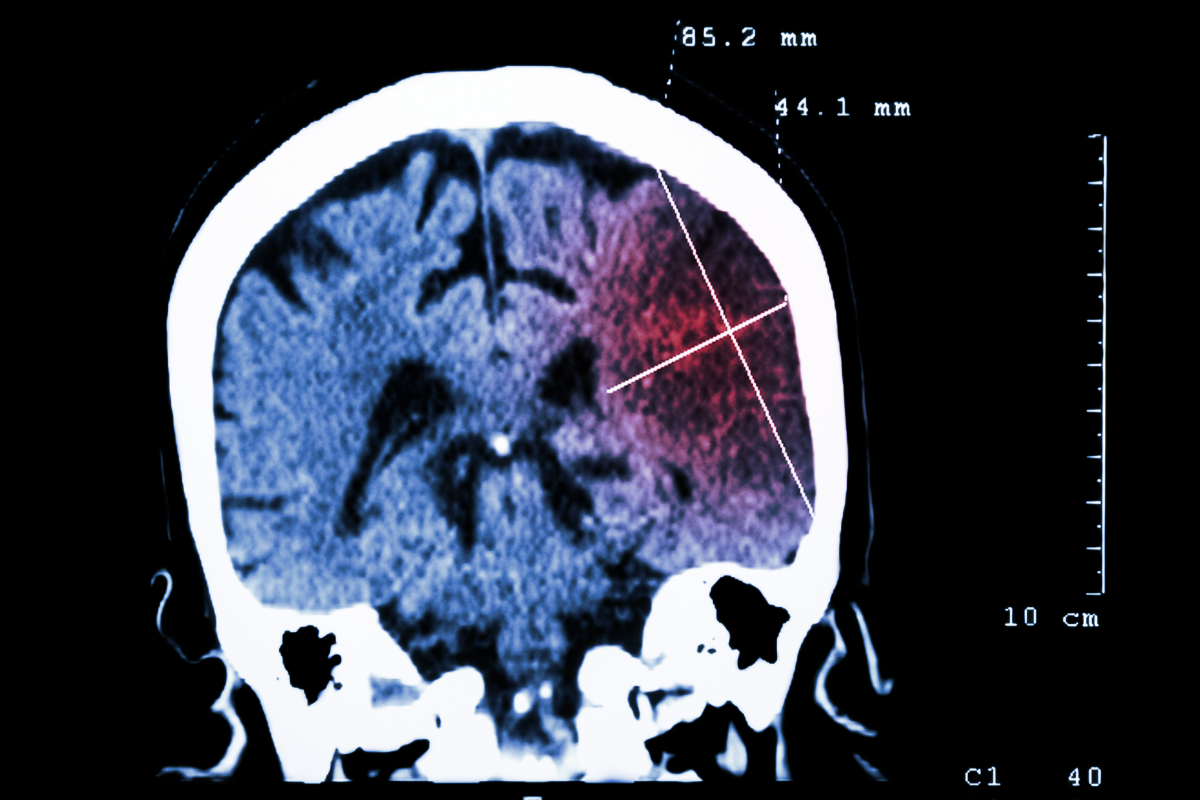

This minimally invasive surgical tool removes hematomas with low tissue disruption, protecting parts of your brain that control speech, memory and vision. The neurosurgeon is able to navigate between the natural folds in the brain and map the exact location of the tumor or blood clot using imaging. Then, through an opening no larger than a dime, the neurosurgeon can remove the clot or tumor from the deepest recesses of the brain without cutting or damaging anything else in its path.

Stereotactic radiosurgery uses many precisely focused radiation beams to treat tumors and other problems in the brain, spine and other parts of the body. It is not surgery in the traditional sense because there's no incision; it uses 3D imaging to target high doses of radiation to the affected area with minimal impact on the surrounding healthy tissue. The procedure works by damaging the DNA of the targeted cells. The affected cells then lose the ability to reproduce, which causes tumors to shrink.